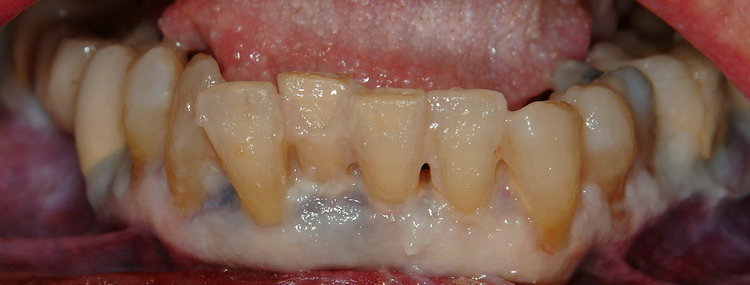

Нижняя челюсть.

навскидку это молодая женщина, не старше 25 лет, хотя фотографии не очень - плохо видна жевательная поверхность. Нет указания в условии на прикус

А пока, с учетом тех трудностей, которые имеются, недостаточным обзором большинства зубов, появление полоски дентина на всех резцах и начальные почвления дентина на клыках, отсутствие правой нижней 6(если правильно разглядел) - возраст примерно 31-35лет.

По фотографии 20-25.

Совсем другое дело. Изменяю возраст на 25-30л.

По таблице получается 25-30 лет.

Но вот смотрю я на пломбы. Сейчас уже такие не ставят, ставили в годах 90-х. Может тогда около 35-40 лет. Но это так от себя.

Уважаемые Мих, Filin, Vitalykk, smed!

Большое вам спасибо за участие в тестировании "зубной таблицы" г-на Маскина П.А.!

Женщину однозначно идентифицировали. Выставил этот случай на всеобщее обозрение потому, что уже на вскрытии мы все с удивлением разглядывали эти зубы. Труп типичной старушки с остеопорозом, выраженным атеросклерозом аорты, возрастной эмфиземой лёгких. Мы попожимали плечами, головами покачали, но всё объяснить в биологии нельзя. Наш шеф ещё сказал, что эта женщина видимо никогда не "обдирала" зубной налёт зубными щётками и не "травилась" зубной пастой. По внешнему виду и по сотоянию внутренних органов старушке было явно за 60 лет. Видя это несоответствие я и решил выставить этот, с моей точки зрения, интересный случай на форум. У меня есть и фотографии трупа, но выставлять их не хочу, т.к. по внешнему виду трупа можно идентифицировать личность, что противоречит правилам форума, да и здравому смыслу.

Теперь нам сообщили возраст этой старушки.

Господа эксперты! На фотографиях вы видите зубы 82 летней женщины.